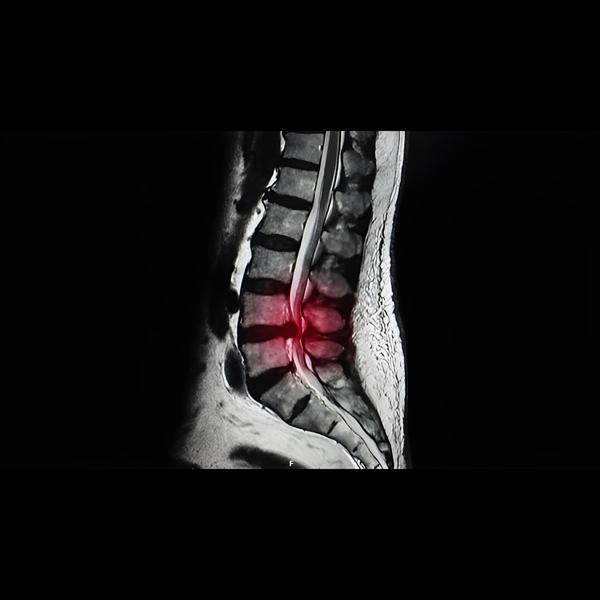

Spinal Surgeries in Dadar

Advanced Herniated Disc Surgery in Mahalaxmi for S...

Comprehensive Spinal Surgeries in Parel for Lastin...

Reliable Spinal Stenosis Surgery in Tardeo for Com...

Spinal Stenosis Surgery in Mahim – Restore Comfort...

Spine Surgery Specialist in Khar – Advanced Solutions for Back and Neck Disord...

Endoscopic Spine Surgeries in Lalbaug – Minimally ...